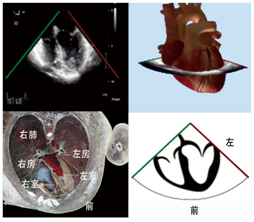

超声主机屏幕和出版物上的TEE图像通常被默认属于室内空间,室内空间的方位和坐标和人体空间不同,造成切面、心脏模型和人体空间之间的联系难以理解和交流,因此,TEE图像应该遵循二维或三维切面解剖学的原则,将TEE图像还原到患者的解剖空间,统一人体方位、心脏模型和超声切面。

什么叫超声容积探头围手术期经食管超声心动图监测操作的专家共识(可下载)_https://www.jmylbn.com_新闻资讯_第22张什么叫超声容积探头围手术期经食管超声心动图监测操作的专家共识(可下载)_https://www.jmylbn.com_新闻资讯_第23张

图2  2D和3D图像及成像原理图3食管中段4腔心切面及模型图

2D或是3D图像(图2)都需要定义观察者视角,一般采取面对心脏模型的观察者视角,统一观察者视角有2个理由:1.观察者面对心脏模型与系统解剖学方位一致,便于沟通;2.不同观察者面对心脏模型有利于实现从TEE到TTE的快速切换。以食管中段4腔心切面为例,描述探头与图像的位置关系理解图像和心脏模型的位置关系(图3),直观地显示了探头、切面与心脏模型的空间关系。